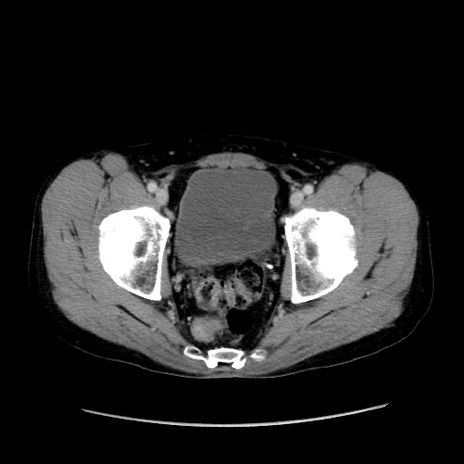

症例37(横断像)

【症例】40歳代 男性

【主訴】腹痛

【現病歴】4時間ほど前に電車に乗車中に臍部上より腹痛出現。徐々に増悪し起立困難となり、救急外来受診。生ものは数日食べていない。今朝お雑煮を食べた。

【身体所見】BT 36.8℃、BP 117/84mmHg、HR 91/min、SpO2 97%、苦悶様、腹部:臍上部広範囲圧痛あり、反跳痛±

【データ】WBC 8100、CRP 0.03